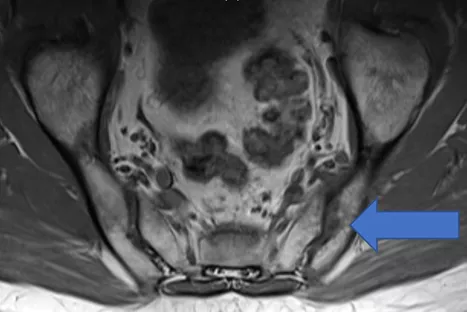

中年男性に発症した、単関節炎とその周囲炎(Psoriatic onycho-pachydermo periostitis:POPP)。血清反応陰性で、尿酸値は正常。尋常性乾癬あり、足趾に爪病変をみとめた。また詳細な病歴聴取にて2週間前から炎症性腰背部痛を認めたため、脊椎の側面および骨盤正面単純X線検査を行うも異常なし。その後仙腸関節および全脊椎MRIを施行し(図3a:T2FS, b:T2FS, c:T1)、左仙腸関節に骨髄浮腫の所見を数スライスにわたりみとめ、X線基準を満たさない体軸性脊椎関節炎(体軸性乾癬性関節炎)と診断した。

図3a,b,c 仙腸関節MRI